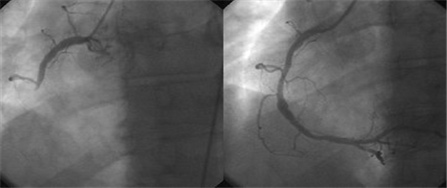

우리 오산한국병원 심혈관센터는 혈관조영촬영 장비를 도입하며 출발했으며 오산지역 유일의 심장내과 진료가 가능한 종합병원으로 관상동맥조영촬영, 관상동맥중재시술을 수차례 시행하며 지속적인 발전을 거듭하고 있습니다.

관상동맥이란 심장의 바깥을 둘러 싸면서 심장에 산소와 영양분을 공급해 심장의 기능을 유지하는 중요한 혈관입니다. 관상동맥질환은 이 혈관들에 죽상 동맥경화증으로 인해 협착이 생겨 심장 근육의 혈류 공급에 장애가 생겨 흉통이나 호흡 곤란 등의 증상으로 나타나고, 심할 경우 심장마비, 사망까지 이르기도 합니다.

관상동맥질환은 서구에서는 이미 오래 전부터 가장 흔한 사망원인으로 알려져 있고 최근 우리 나라에서도 생활의 서구화에 따라 그 빈도가 급격히 증가하는 추세에 있어 그 중요성과 심각성이 부각되고 있습니다.

관상동맥질환으로 인한 흉통, 실신, 호흡곤란 등이 발생하였다고 생각되는 경우에 관상동맥질환을 확진하는 가장 정확한 검사이며, 향후 치료법을 결정하는데 아주 중요한 검사입니다. 심혈관조영술은 대부분의 심장 질환을 진단하고 심장의 기능 및 형태에 관해 정확하고 자세한 정보를 제공합니다.